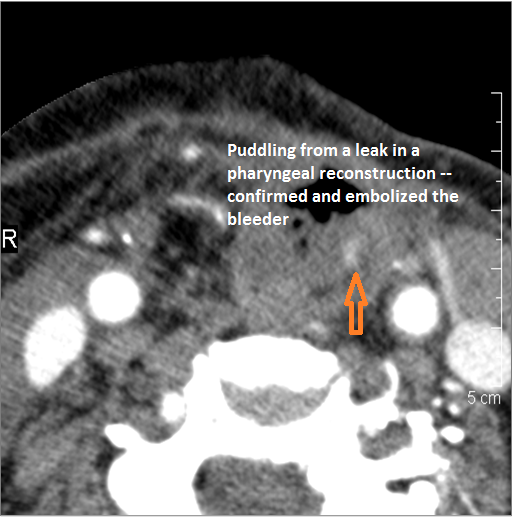

There is evidence of a contained leakage from an arterial source. |

No | NA |

There is evidence of active extravasation from an arterial or venous source. |